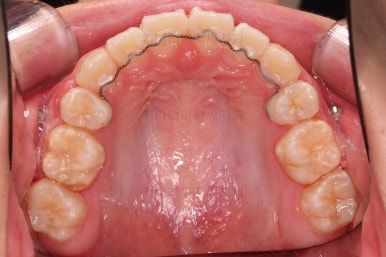

초진 시, 입 안의 모습입니다.

치아가 많이 삐뚤어요.

공간이 부족해서 앞니가 앞으로 많이 뻐드러졌고, 삐뚤한 양상 때문에 덧니가 되었네요.

어금니 맞물림도 좋지 못한 앵글씨 2급 부정교합 상태였어요.